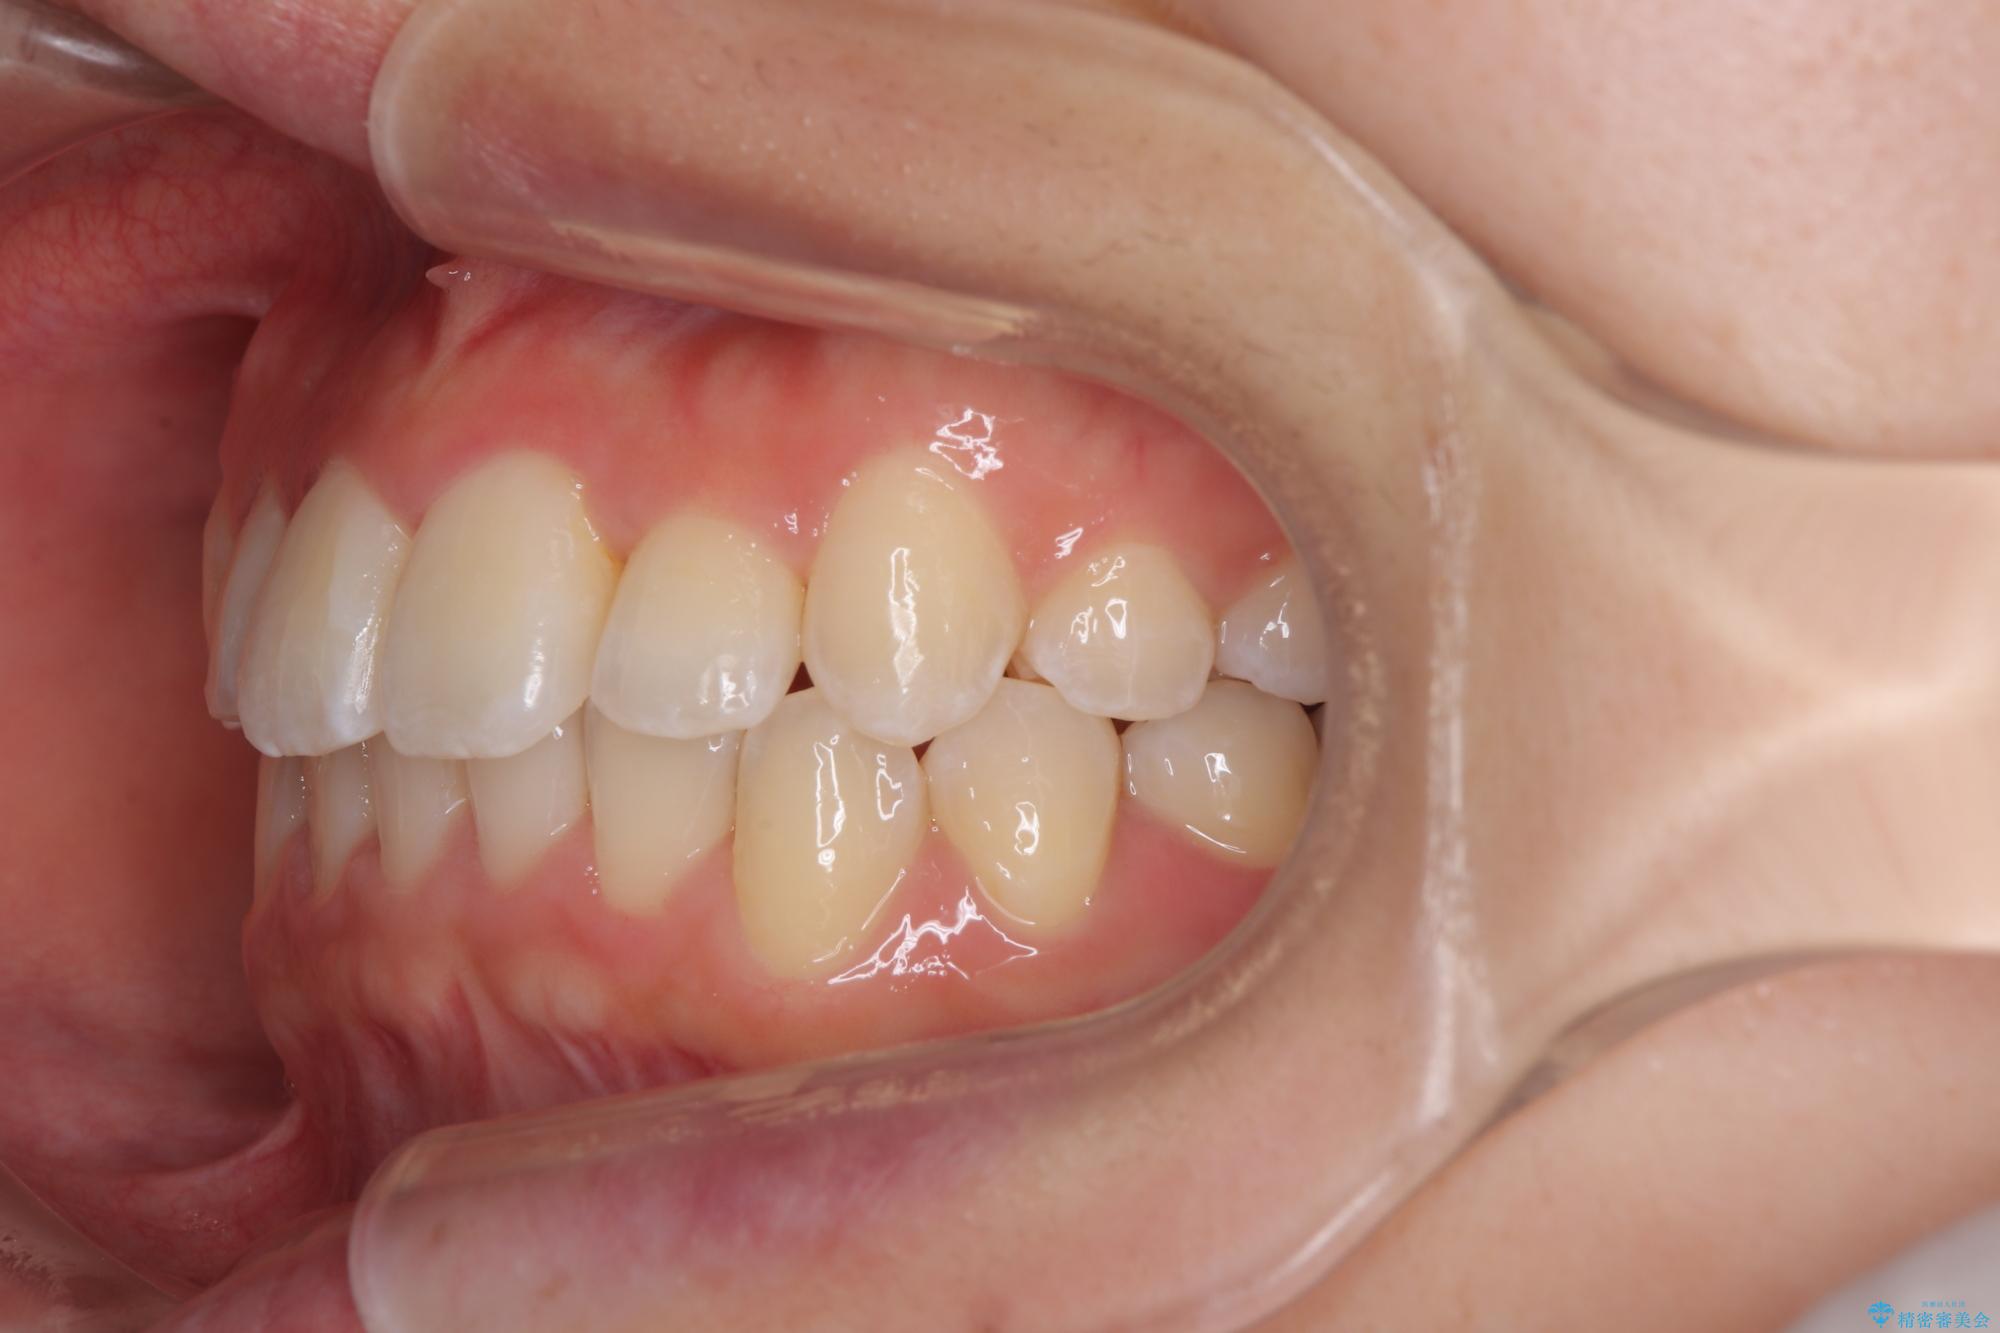

前歯のクロスバイト 裏側に隠れた歯をワイヤー装置で短期間治療

- 上顎前歯のクロスバイトを気にして来院された患者様です。

ワイヤー矯正でもマウスピース矯正でも対応可能でしたが、マウスピースによる自己管理に一切の自信がないとのことで、ワイヤー装置にて矯正治療を行うこととしました。